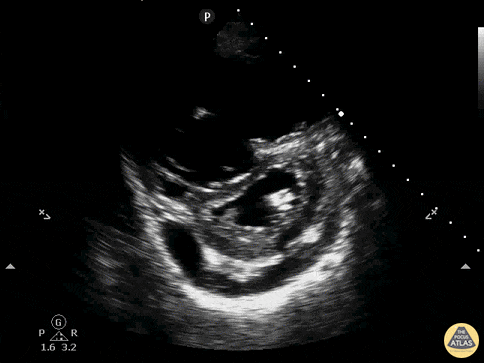

A 62-year-old with metastatic cancer presents with abrupt dyspnea, pleuritic chest discomfort, and near-syncope. Vitals: T 37.2°C, HR 132, BP 88/54, RR 32, SpO₂ 85% on room air. Exam: anxious, cool extremities, elevated JVP, clear lungs on auscultation, and no focal crackles. A parasternal short-axis PoCUS clip is shown.

Describe what is seen and its pathophysiology?

What is acute right ventricular pressure overload causing RV dilatation and interventricular septal flattening that bows into the LV, producing the D-sign and impairing LV filling, together with a pericardial effusion representing fluid accumulation in the pericardial space (2/2 to malignancy) that can further restrict cardiac filling and worsen hemodynamics?